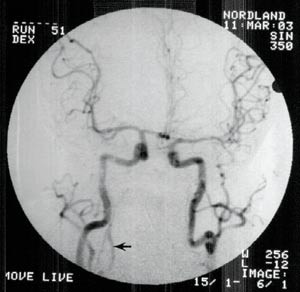

Angiography with contrast injected into the aortic arch showed preserved circulation in both internal carotid, middle and anterior cerebral arteries, but absence of basilar artery circulation. A cerebral CT scan was initially normal, but 14 hours later a new scan demonstrated infarction of the brain stem, cerebellum and occipital lobes. The Norwegian criteria for organ donation were not fulfilled as these require stop of all intracranial circulation. The respirator was disconnected and the patient died.

Det ble så, 24 timer etter hendelsen, utført arkografi som viste god sirkulasjon gjennom begge carotisarterier og i begge arteriae cerebri media og anterior (fig 2).

Ny cerebral CT ca. 25 timer etter hendelsen viste utbredt infarsering av hjernestamme, cerebellum og begge oksipitallapper samt begynnende hydrocephalus (fig 3). Gransking av arkografiundersøkelsen viste ingen fylling av venstre a. vertebralis og bare en meget langsom fylling av sentrale deler av en tynn høyre a. vertebralis. Det var ingen kontrastfylling av a. basilaris (fig 2).